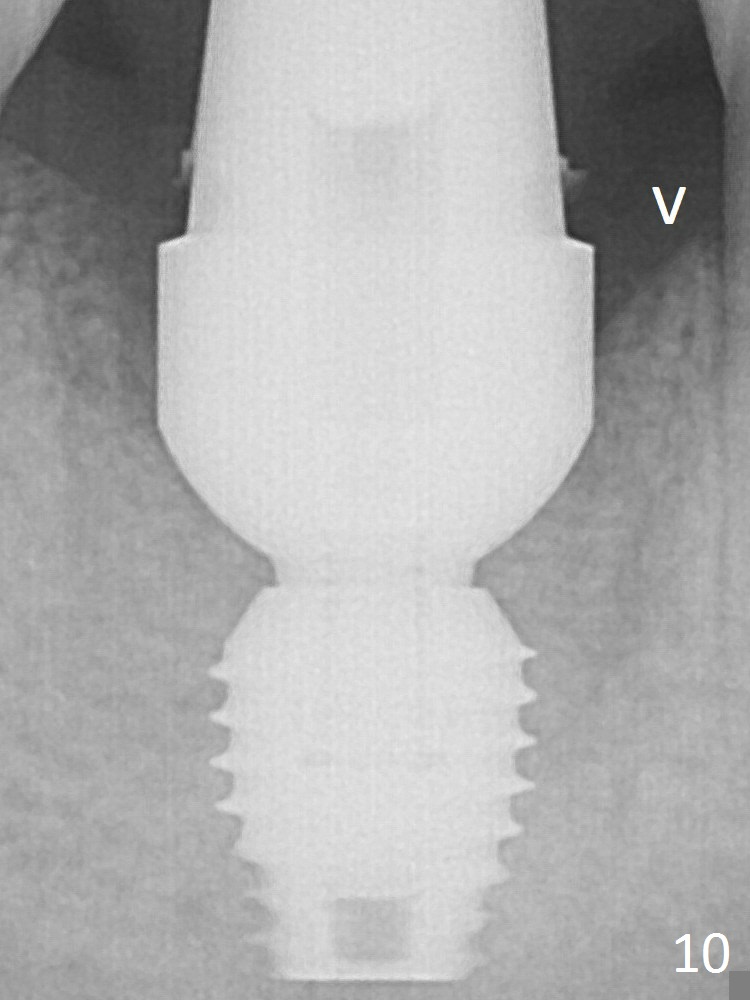

Then bone graft (Fig.7 *) and 7.8x5.5(6) mm abutment are placed.

The bone density around and above (Fig.10 arrowhead) the implant increases 2 months postop.